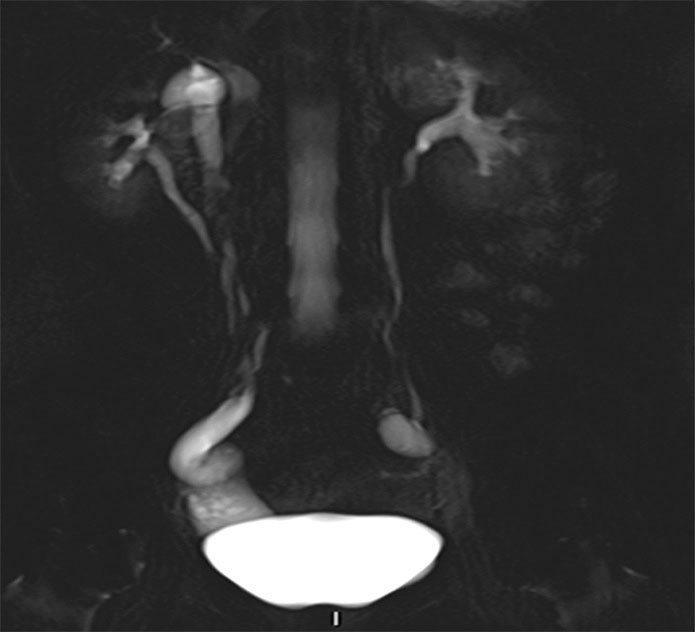

CT av urinveier ble utført, men det var ikke mulig å gi noen konklusjon med hensyn til ektopisk munnende ureter. Det ble derfor utført MR av urinveiene. Det forelå dobbeltanlegg på høyre side med et lite øvre anlegg og et dilatert ureter (fig 1). Ureter forløp dilatert mellom urinblære og vagina og munnet ut ektopisk nær urethras utmunning (fig 2).

For å identifisere dobbeltanlegg og ektopisk munnende ureter på CT forutsettes tilstrekkelig funksjon og kontrastutskilling fra det øvre anlegget, noe som ikke var tilfellet for denne pasienten. Ultralyd kan identifisere dilatert, ektopisk ureter, men det kan være vanskelig og krever som regel spesiell oppmerksomhet. Vår pasient var henvist med spørsmål om kolelitiasis og pyelonefritt, og det ble ved rutinemessig vurdering av urinveiene ikke oppdaget patologi. Høyoppløselige væskesensitive MR-sekvenser i volumopptak gir gode forutsetninger for å identifisere ureter og følge ureters forløp. I det lille bekken er MR bedre egnet enn CT, men mer tidkrevende. Det ble utført dedikerte høyoppløselighetsserier i bekkenet supplert med mindre detaljrike sekvenser over øvre urinveier. Det ble ikke benyttet kontrastmiddel under MR-undersøkelsen. Barnelegene bruker MR som primær modalitet ved mistanke om ureteral ektopi.

Årsaken til pasientens vedvarende problem med urinlekkasje var altså et ektopisk munnende ureter (fig 3).